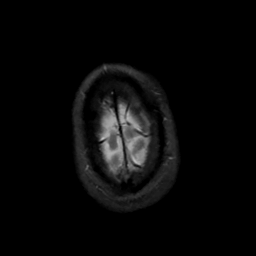

MR Study #5, March 10, 1991 -- Slice #48

[Home][Help][Clinical][Tour 1][Tour 2] Slice 48